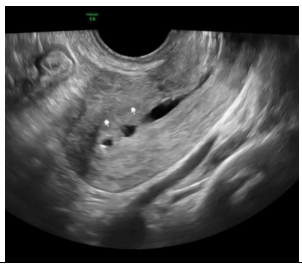

Paciente de 33 anos, comparece ao pronto atendimento com queixa de dor abdominal aguda de moderada intensidade. Nega comorbidades, nega uso de medicações, refere atraso menstrual de 20 dias. Na avaliação ecográfica apresenta a seguinte imagem:

A imagem ecográfica se correlaciona com diagnóstico de